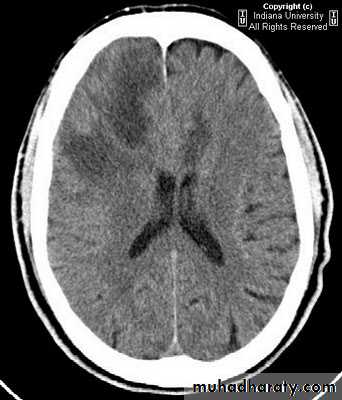

• Computed Tomography (CT-scan):

• Site and size of the tumour.

• Boundaries of the tumour.

• If there is surrounding oedema or not.

• Shift of the midline structures by the mass.

• Associated hydrocephalus.

• Bony changes.

• Nature of the tumour (solid, cystic, necrotic or calcified), and so its pathology.